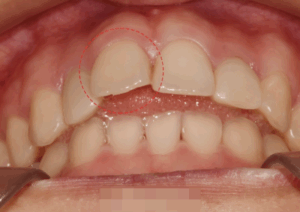

회전된 앞니, 교정과 전문의가 있는 상봉동 치과 에서 어떻게 치료를 도왔을까?

『가운데 있는 중절치가 회전되어 있고 기울어져 있다면 보기 좋을까요?』 안타깝지만 고른 치열에 비해 좋지 않은 이상을 줄 수밖에 없습니다. ​ 특히나 눈에 잘 띄는 곳에 위치해 있어 스스로 위축되거나 치열을…